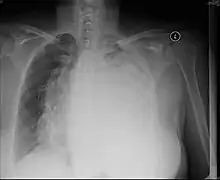

Post-operative changes

A pneumonectomy is a surgical procedure in which an entire lung is removed. A common reason for performing this procedure is for lung cancer originating in the lung itself.[19] This leads to a mediastinal shift towards the empty side of the thorax. Notably, patients can experience postpneumoectomy syndrome due to a severe mediastinal shift. This presents as difficulty breathing due to shift of airways and rotation of the heart and great vessels. On x-ray, white out of the operated side and hyperinflation of the remaining lung is often observed.[20]